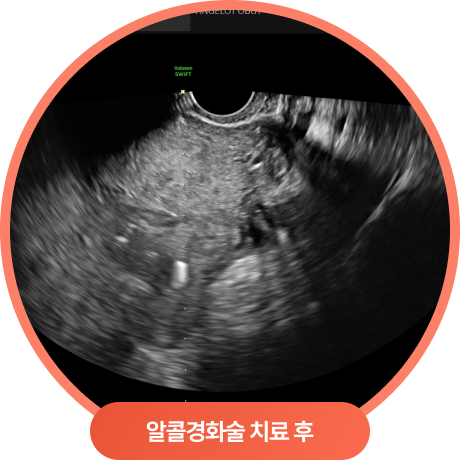

난소낭종 알콜경화술 치료 효과

황체낭종, 자궁내막종

치료 결과

이 케이스 경우 한쪽 난소에서 황체낭종과 자궁내막종이 동시에 발견되어,

두 병변을 모두 알콜경화술로 안전하게 흡입·치료하였습니다.

이처럼 초음파 유도하에 병변을 정확히 확인하고 내용물을 제거한 뒤, 에탄올을 주입하여

재발 가능성을 줄이는 방식으로 난소를 최대한 보존하면서 치료가 가능합니다.